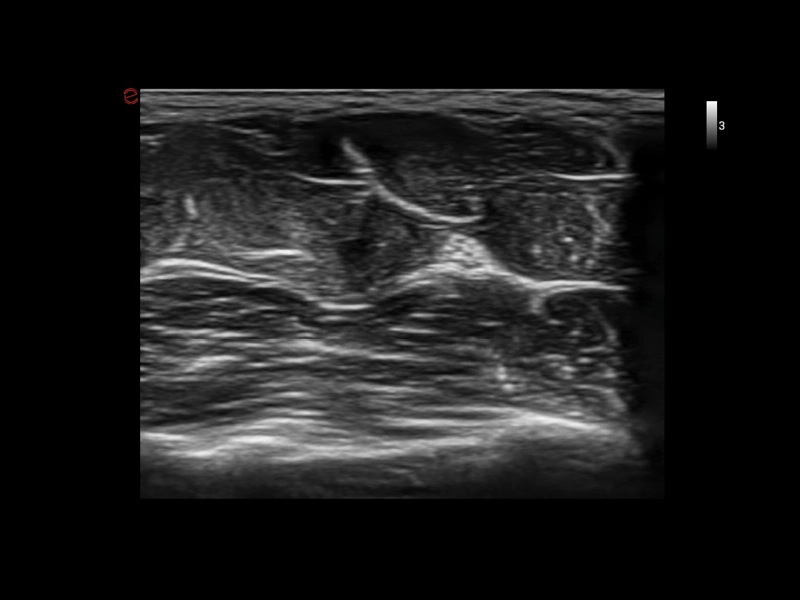

MyLab™Sigma Elite - B-Mode high resolution on median nerve

MyLab™Sigma Elite - B-Mode high resolution on median nerve